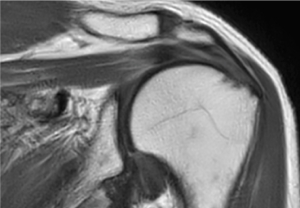

Jestem pod ogromnym wrażeniem wielkiego potencjału rozwiązania SmartSpeed, zwłaszcza w przypadku obrazowania 3D układu mięśniowo-szkieletowego, które staje się teraz możliwe. Krótki czas skanowania i świetna jakość obrazów to podstawa w prywatnym ośrodku diagnostyki obrazowej takim jak nasz”.

Dr Tobias Schröter

MRT-Praxis w Poczdamie, Niemcy